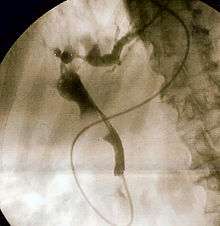

Duodenoscopy image of pus extruding from Ampulla of Vater, indicative of cholangitis | |

The gold standard test for biliary obstruction is still endoscopic retrograde cholangiopancreatography (ERCP). This involves the use of endoscopy (passing a tube through the mouth into the esophagus, stomach and thence to the duodenum) to pass a small cannula into the bile duct. At that point, radiocontrast is injected to opacify the duct, and X-rays are taken to get a visual impression of the biliary system. On the endoscopic image of the ampulla, one can sometimes see a protuberant ampulla from an impacted gallstone in the common bile duct, or the frank extrusion of pus from the common bile duct orifice. On the X-ray images (known as cholangiograms), gallstones are visible as nonopacified areas in the contour of the duct. For diagnostic purposes, ERCP has now generally been replaced by MRCP. ERCP is only used first-line in critically ill patients in whom delay for diagnostic tests is not acceptable; however, if the index of suspicion for cholangitis is high, an ERCP is typically done to achieve drainage of the obstructed common bile duct.[1]